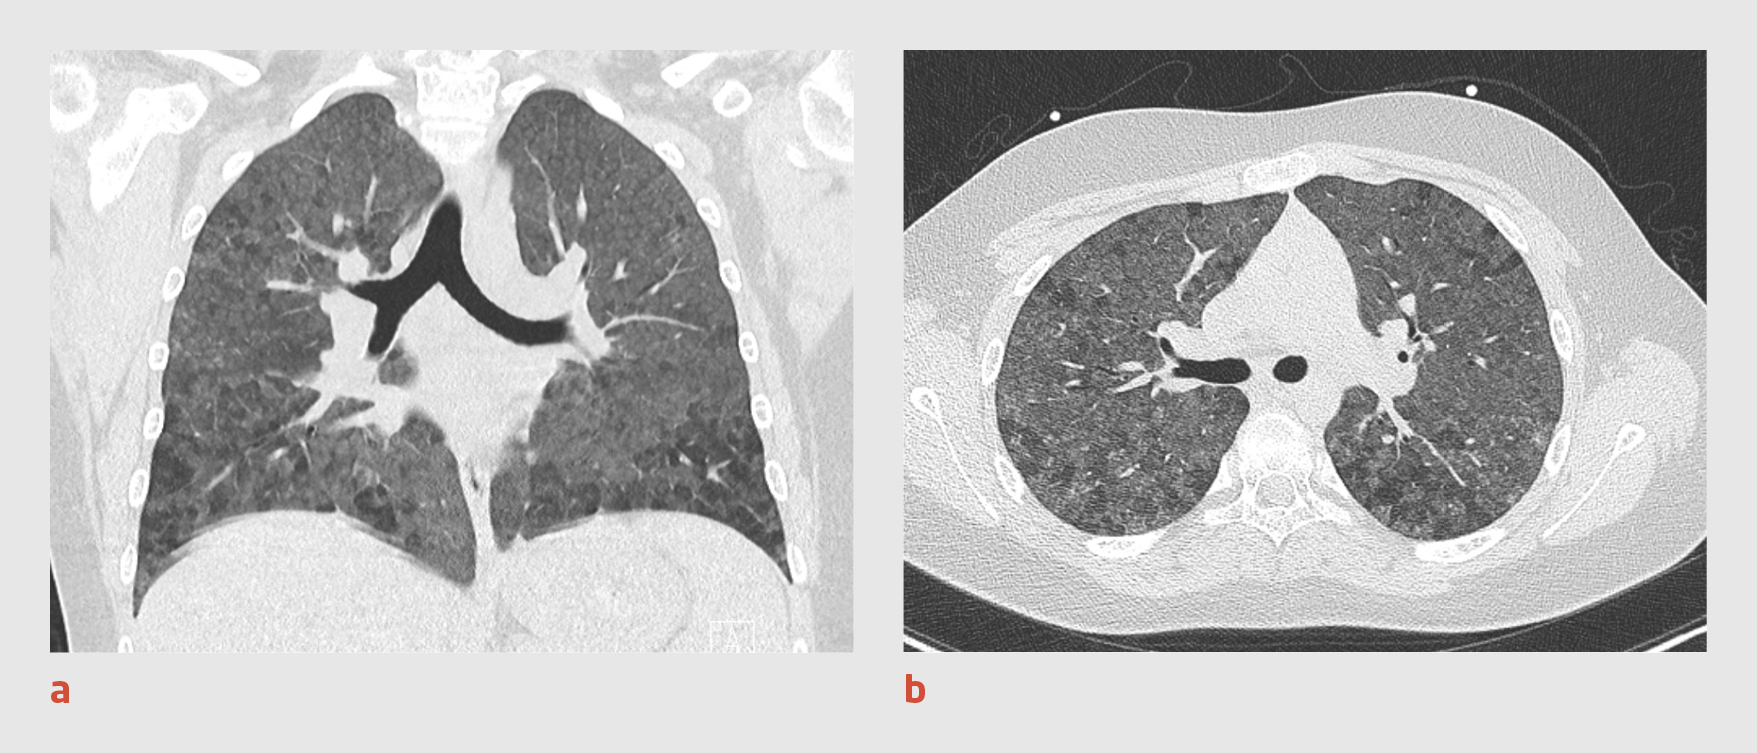

8 dagen later bezocht patiënt opnieuw de SEH, omdat zijn klachten waren verergerd. De uitslagen van het laboratoriumonderzoek waren niet veranderd. Vanwege het vermoeden van een longembolie bij een covid-19-pneumonie werd een CT-scan van de thorax verricht, waarbij intraveneus contrastmiddel werd toegediend. Op de scan was geen longembolie te zien. De afwijkingen met een maglas-aspect waren in omvang zelfs afgenomen, wat niet past bij progressie van covid-19. Ditmaal werden er onscherp begrensde, centrilobulaire noduli met een matglas-aspect gezien, met dynamische hyperinflatie (‘airtrapping’), perilymfatische noduli en symmetrische lymfadenopathie. Deze bevindingen pasten bij een niet-infectieuze, granulomateuze longziekte of een zeldzame, extrinsieke allergische alveolitis, conform een CO-RADS-score van 1.2-4 Vanwege aanhoudende respiratoire instabiliteit werd patiënt overgeplaatst naar de afdeling Intensive Care Kinderen.

Tunnelvisie